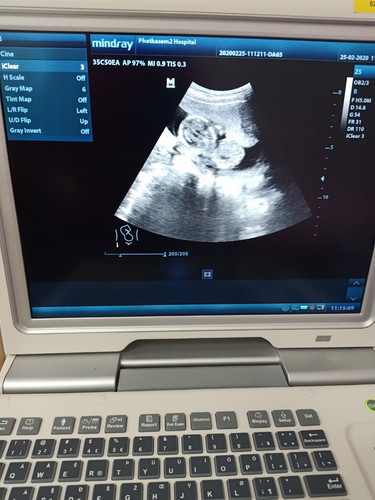

ขอดูภาพซาวด์ของแม่ๆบ้านอ้านอื่นหน่อยค่ะ ตอนนี้14วีค แต่ภาพซาวด์เป็นแบบนี้ปกติของลูกน้อยใช่มั้ยค่ะ??

ภาพตอน 16 วีคค่ะ ล่าสุดซาวด์ตอน 20 วีคน้องหันหลังให้เลยมองไม่ค่อยเห็นอะไรเลยนอกจากหัวกับกระดูกสันหลัง